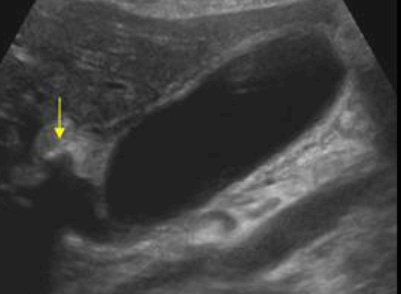

US finding

- 담낭이 비대해지고 담낭벽이 비후 된다

- 담낭 내 격막이 있다